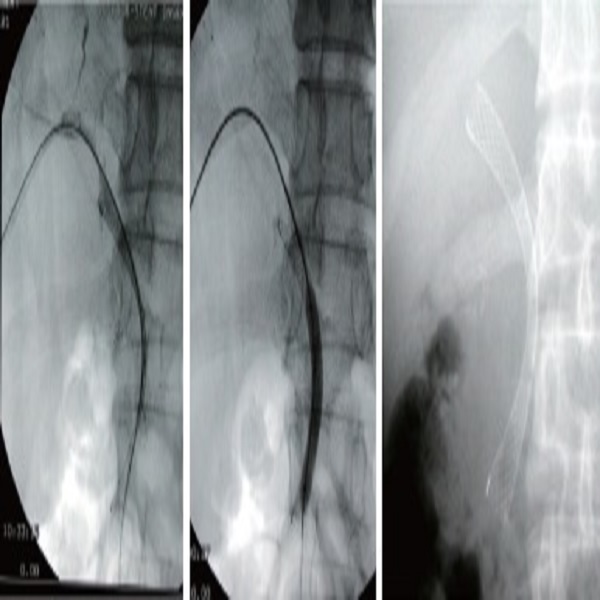

S Biliary Stents Uncovered

-Malignant biliary strictures

-Structure: "Fixed cell with braided construction"-> Flexible and resistant to fracture

-Radiopaque marker : 3(three) at both ends & 2(two) in the middle

-"Palliation of Malignant Biliary and Duodenal Obstruction with Combined Metallic Stenting"

Devrim Akinci: Cardiovasc Intervent Radiol (2007) 30:1173-1177